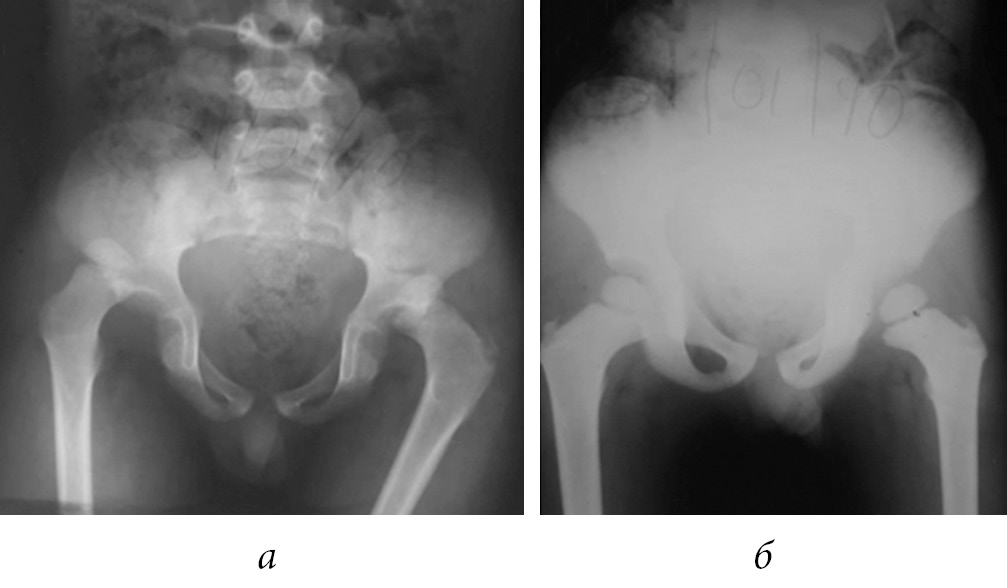

After 12 months, he was asymptomatic, without limitation of mobility arcs, performing daily activities and play without limitations (Fig. 2).

Fig. 2. Pelvis X-ray after 12 months of follow up (a); last X-ray control. Pelvis after 12 years of follow up with skeletal maturity achieved (b)

On follow-up of 12 years after the injury, at the age of 16 years-old presented independent march, without limping; full mobility arcs, a pelvic radiography was obtained and did not revealed any abnormalities.